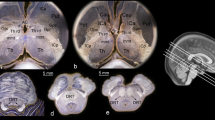

It is instructive to assess the axonal and myelination abnormalities of the AR and volumes of the HG in people with HL. Thus, from the binary segmentations of the left and right HG, volumes were calculated, and from the generated left and right AR, fractional anisotropy (FA) values were calculated at each voxel from the eigenvalues [8]. For the 1.5 T cohort only, the FA values were in the NH, and HL groups were compared using the Wilcoxon-Rank Sum test with 95% confidence interval due to the small sample size and reported with asymptomatic p values with continuity correction. FA values of the AR and HG volumes from subjects with NH (n = 10) and HL (n = 5) are shown in Fig. 4. In the NH group, the FA for the left AR is larger than in the right (0.43 and 0.41, respectively; p value 0.054). The HG volume of the right HG is significantly larger in the HL group compared with the NH group (1122 mm3 and 909 mm3 respectively; p value 0.019).

FA values and HG volumes from 1.5 T cohort of subjects with NH (n = 10) and HL (n = 5). Vertical lines denote maximum and minimum values. The plus sign symbol denotes the mean, and horizontal lines inside boxes indicate the median. Note that volumes of the MGB were not reported due to variability in factors (anatomical size and location), and difficulty of delineation